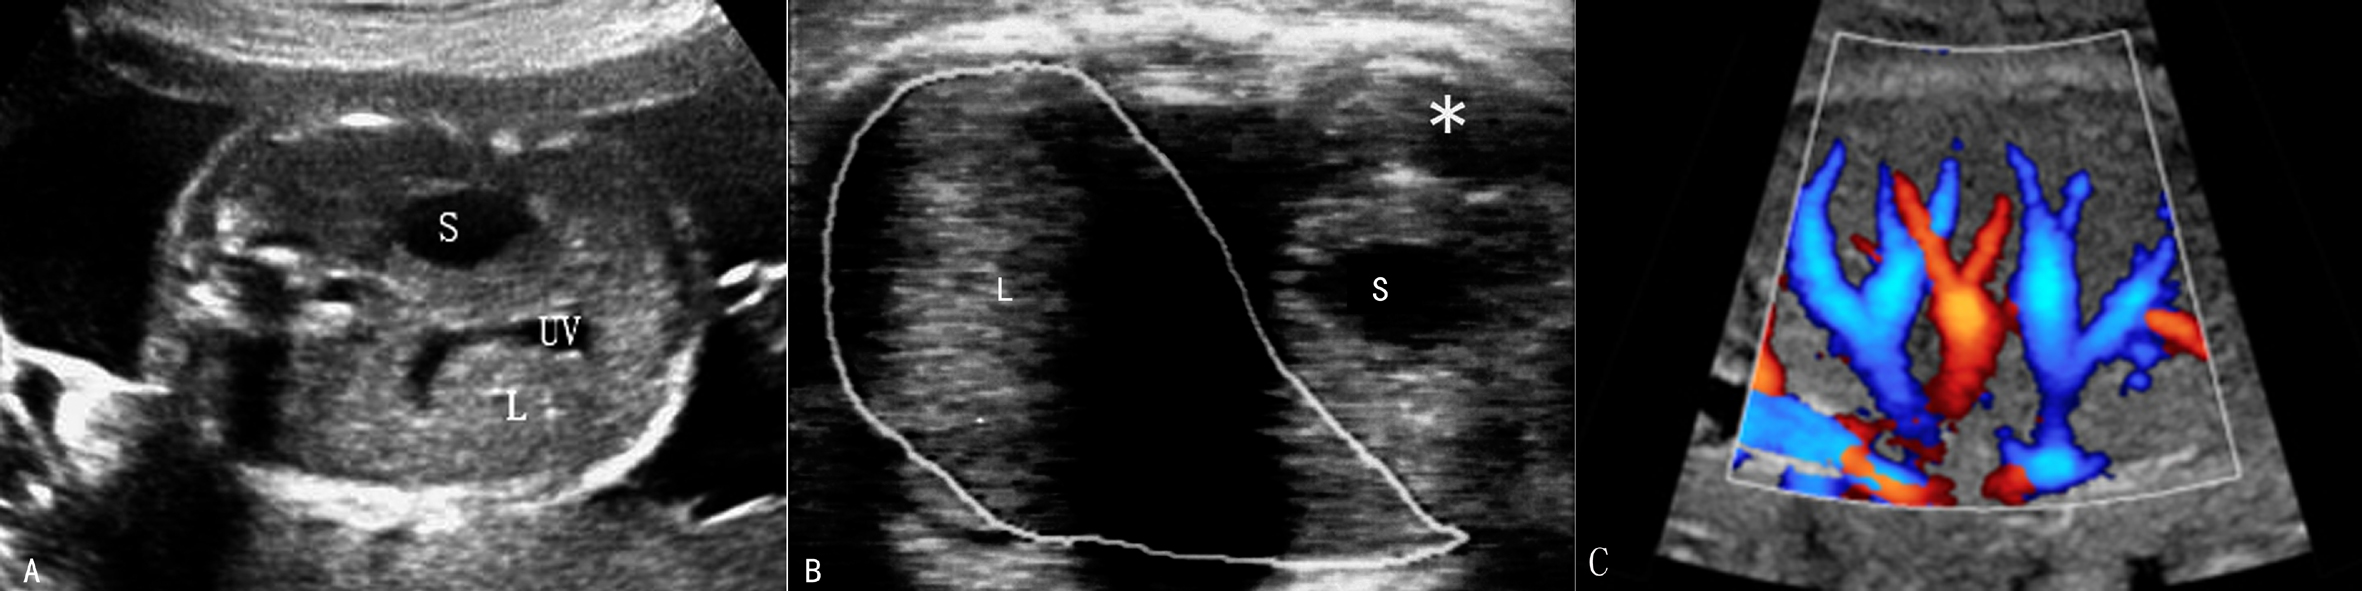

1.肝脏和脾脏 肝脏(L)是胎儿腹腔内最大的实质性器官,几乎占据整个上腹部,横断面占据腹部横截面的三分之二以上(图1A,B)。正常肝脏右叶大于左叶、上部大于下部;左外侧较尖锐,右侧圆钝;表面光滑、清晰;内部显示与成人肝脏相似的中等偏强的回声,分布均匀;第一肝门区可见门静脉进入肝脏,在第二肝门区可见肝静脉进入下腔静脉;在肝脏左叶可显示脐静脉进入肝脏(图1C)。

在肝左侧外侧、胃腔无回声(S)的后上方可见半月形的脾脏低回声(*),形态规则,边缘清晰,内部回声均匀(图1B)。

图1 胎儿上腹部横切面声像图